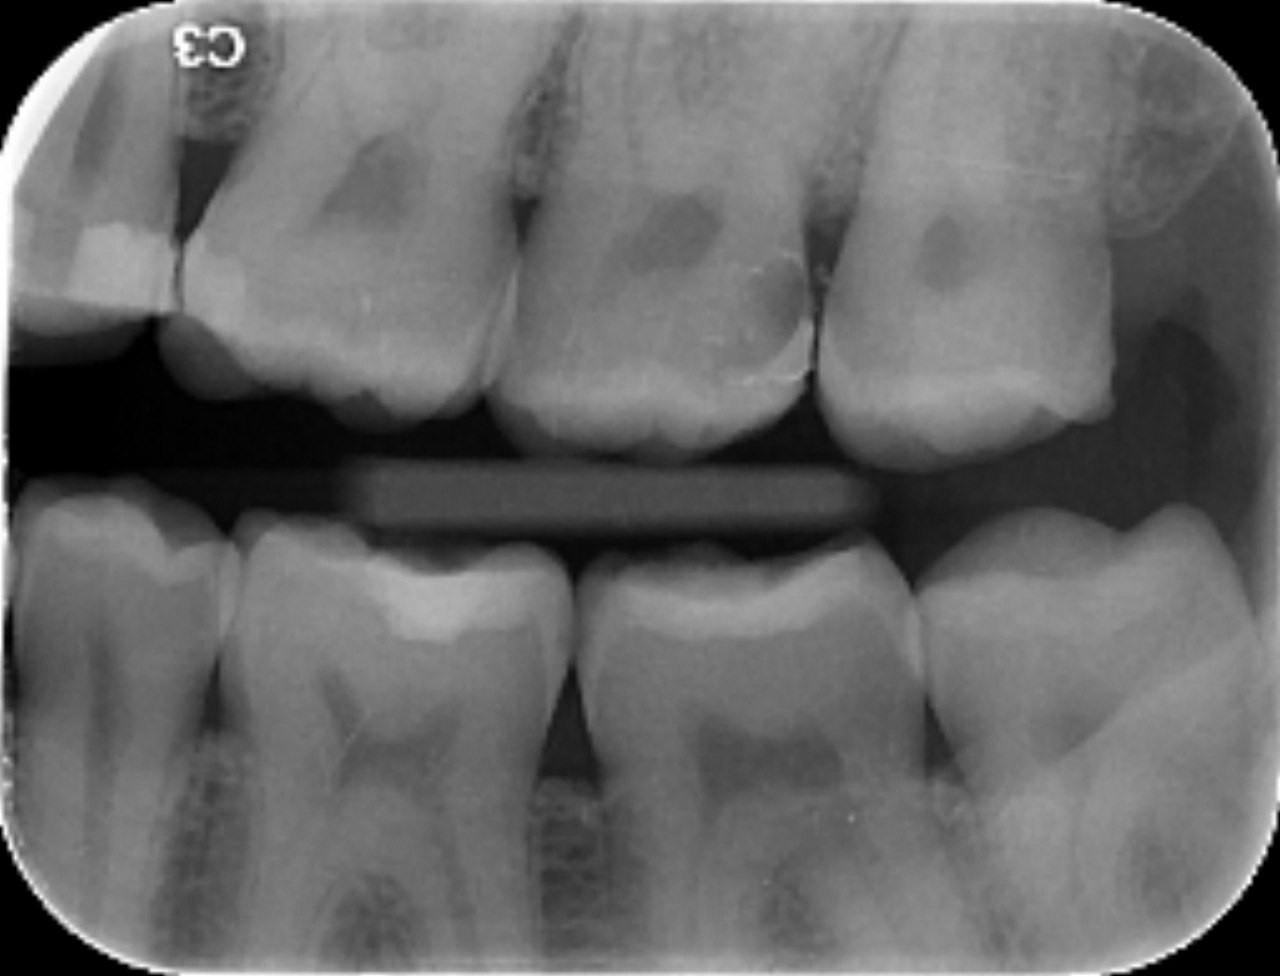

3. What is the caries level on the distal surface of the tooth # 3.6?

6: What is the caries level of mesial of the tooth # 3.6?

7: What is the caries level of Distal of the tooth # 3.6?